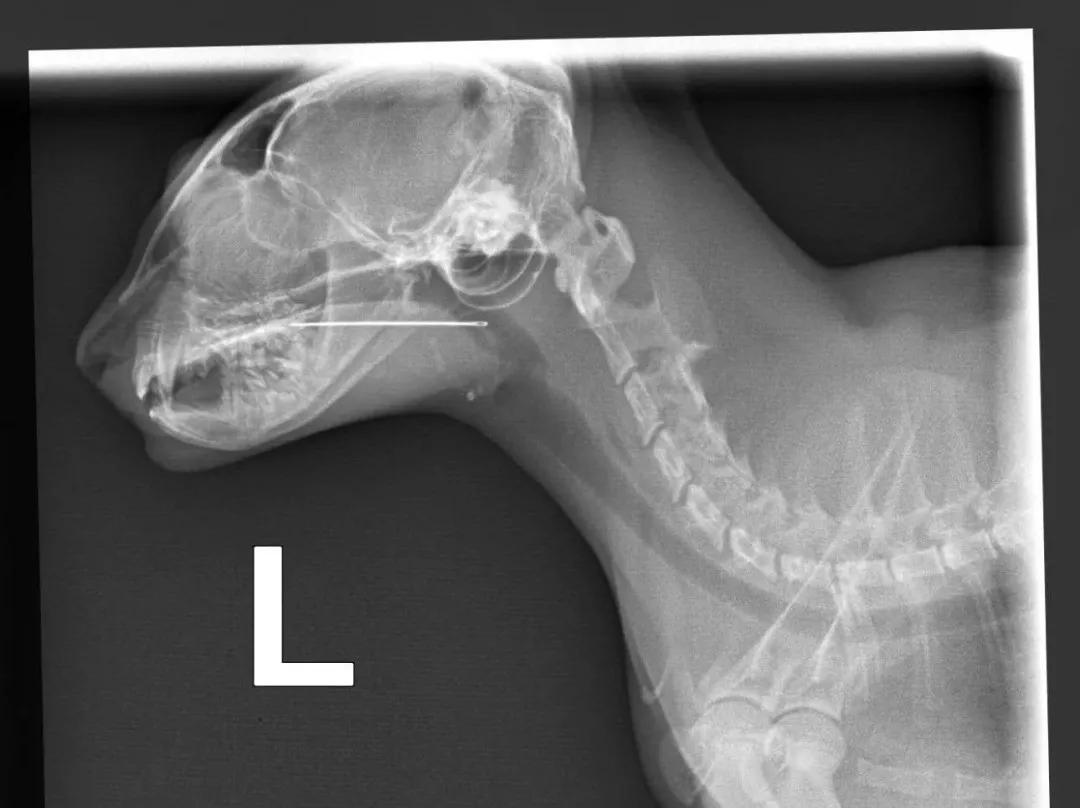

拍了X光才发现,针已经卡在喉咙上了↓

还好卡的位置比较浅,打完麻醉后,医生顺利地把针取了出来。